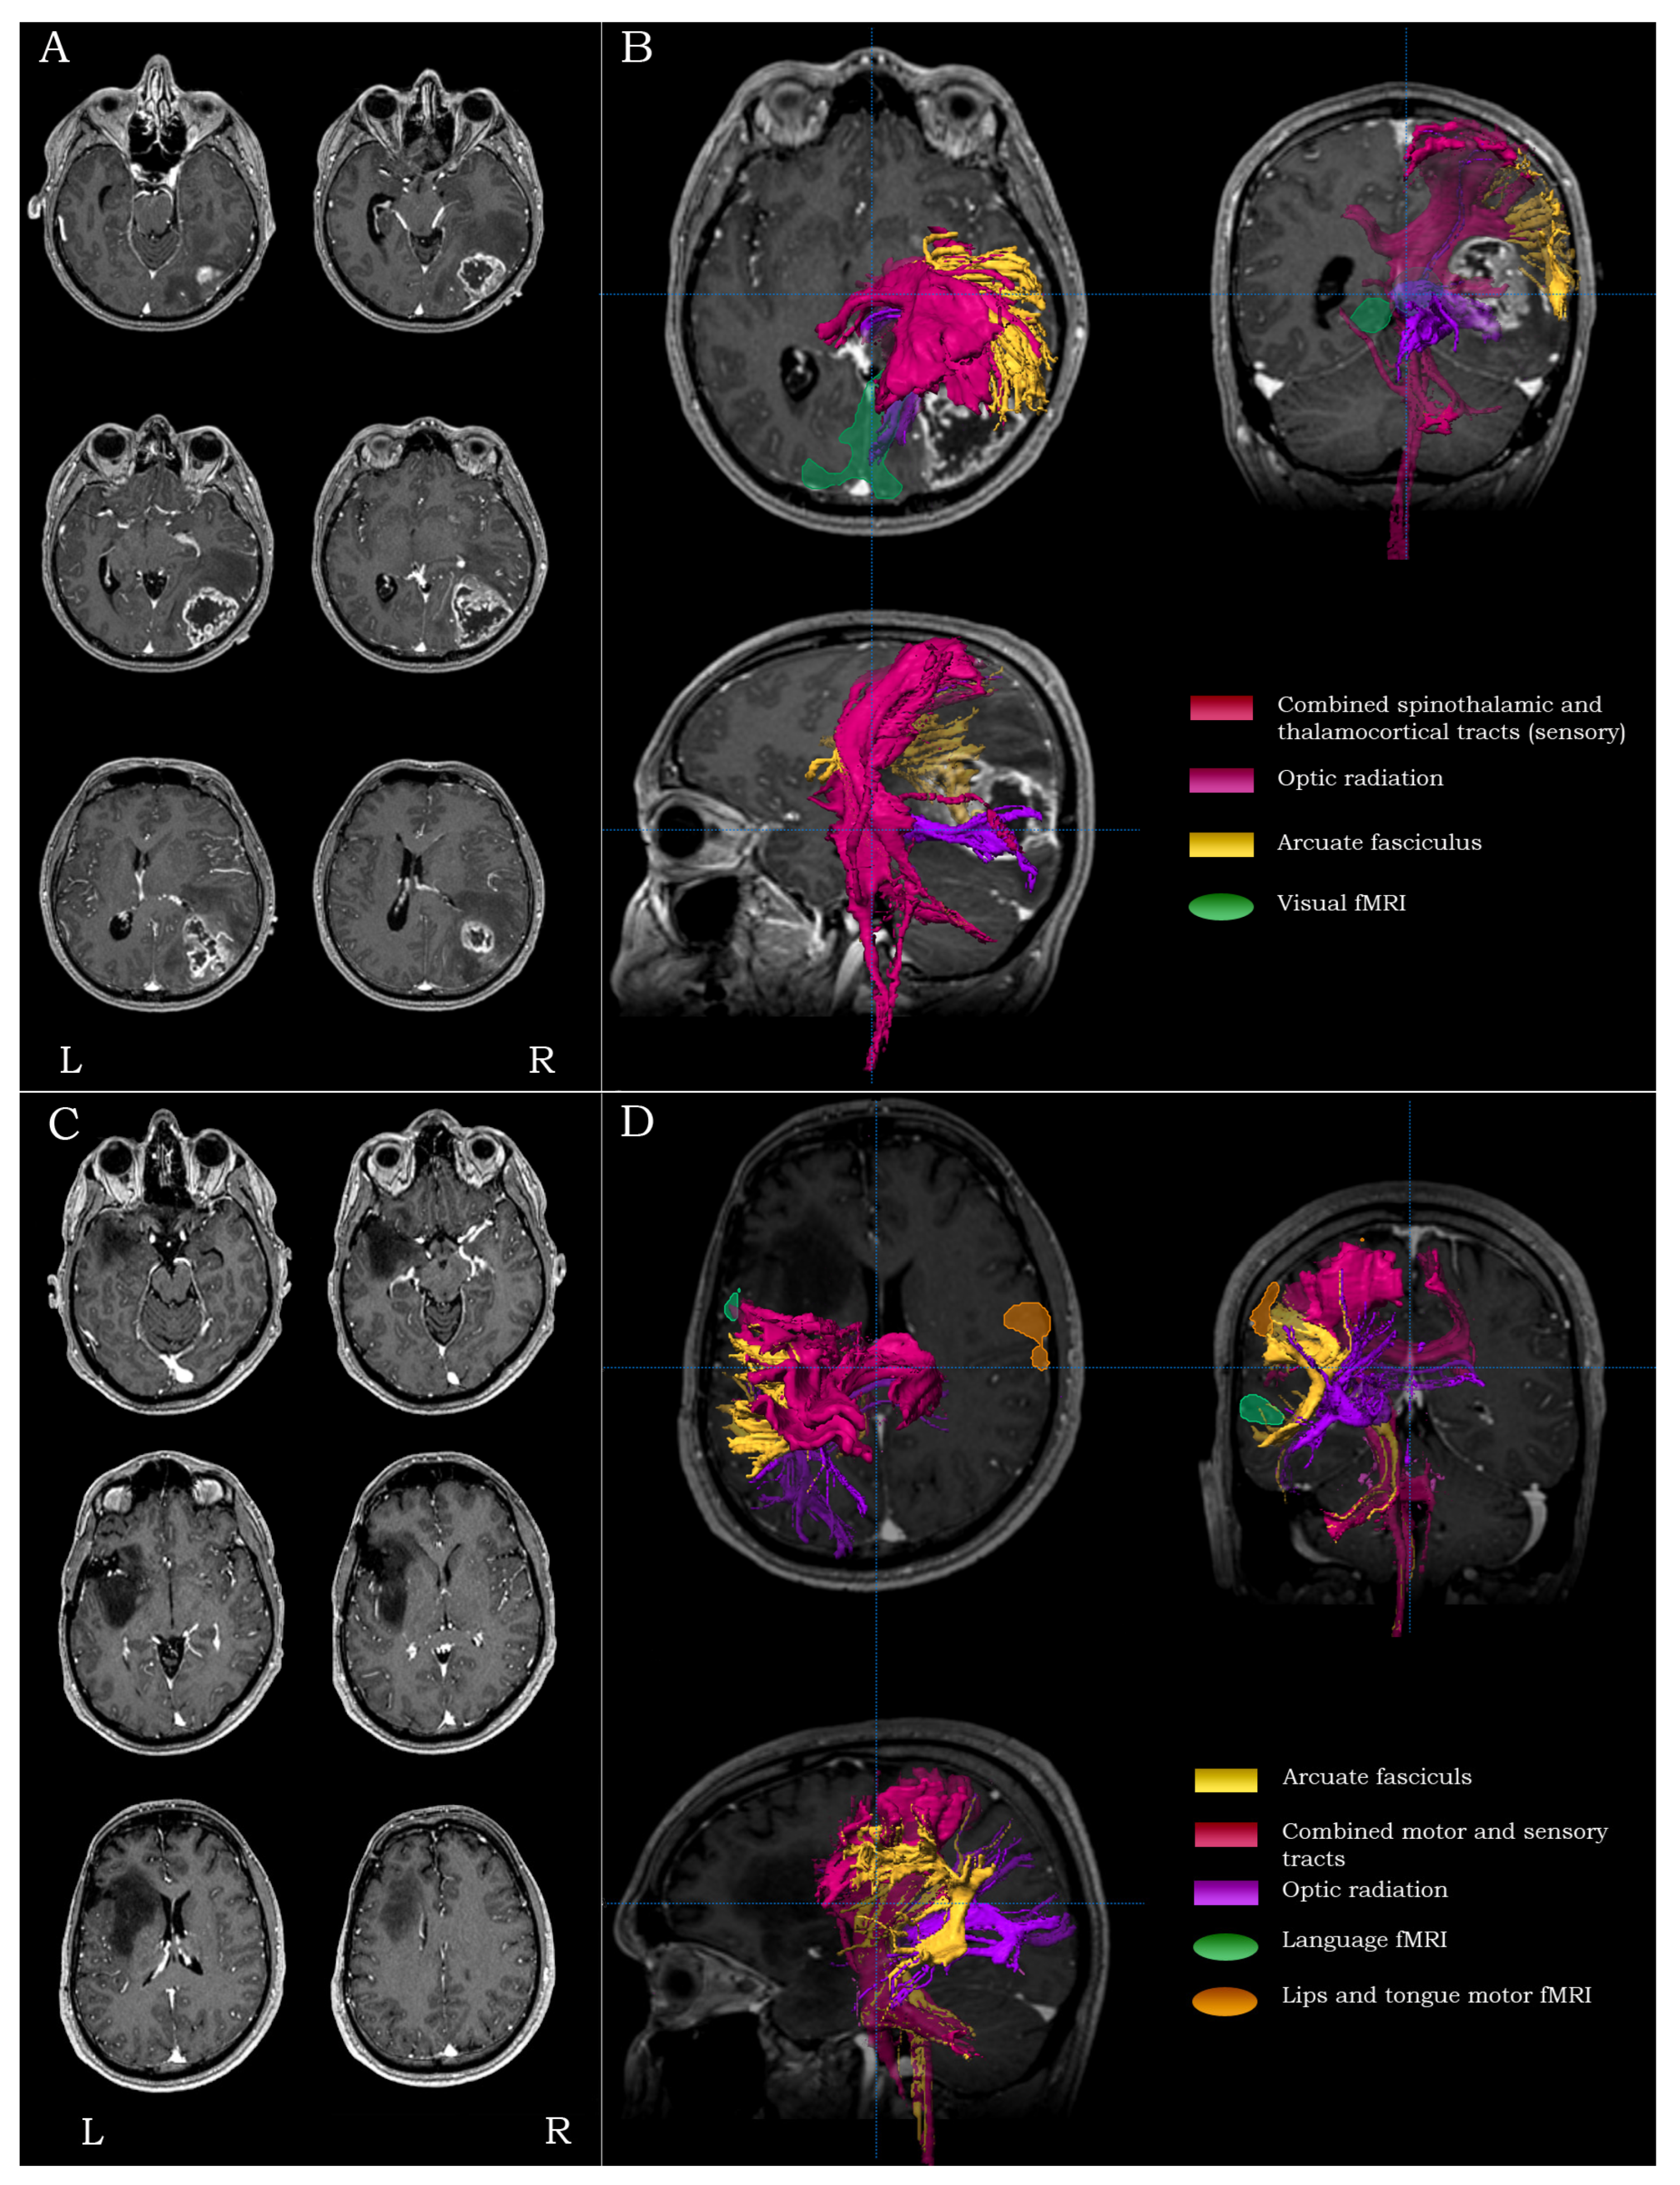

2.5.4. Inferior Parietal/Posterior Temporal Lesions

For lesions residing in the inferior parietal lobule/posterior temporal region (Brodmann areas 39, 40, 41, 42 and 22), especially in the language-dominant hemisphere, the main surgical concerns were the proximity to Wernicke’s area, the proximity to the inferior post-central gyrus and the integrity of the arcuate fasciculus. For such lesions, the mapping process included language fMRI and DTI-tractography of the ipsilateral arcuate, the combined spino-thalamic/thalamo-cortical tracts (optionally accompanied by the cortico-spinal tracts, depending on the anterior extent of the lesion) and the optic radiation (Figure 3C,D).

2.5.5. Temporo-Occipital Lesions

For lesions residing in the temporo-occipital regions (Brodmann areas 19, 30 and 37), the main surgical concerns were the proximity to primary visual and receptive language areas, the proximity to the primary somatosensory cortex and the integrity of the optic radiation. For such lesions, the mapping process included visual fMRI (and language fMRI depending on the extent of the lesion), as well as DTI-tractography of the arcuate fasciculus, the combined spino-thalamic/thalamo-cortical tracts and the optic radiation (Figure 4A,B).

2.5.10. Lesions Extending in Two Lobes

For lesions of extended spatial distribution, the main surgical concerns were the proximity to surrounding eloquent areas and the integrity of tracts in the immediate peri-lesional vicinity. For such lesions, the mapping process included fMRI and DTI-tractography to highlight the location of all the relevant and critical regions/tracts surrounding the lesion (Figure 4C,D).